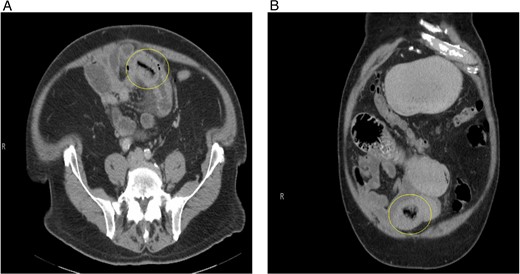

The postoperative course was complicated by ileus, which did not resolve until postoperative day 11. The patient was discharged in stable condition and returned to the hospital 3 days after with oral administration intolerance. At this time, abdominal examination revealed significant abdominal distention. Incisions were healed and non-tender. A repeat abdominal CT scan showed dilated fluid-filled loops of the small bowel consistent with high-grade small bowel obstruction and focal intussusception of a loop of the small bowel distal to the small bowel anastomosis with associated wall thickening (Fig. 2). Over the next two weeks, the patient had a tumbling small bowel obstruction. His abdominal symptoms improved and worsened cyclically. A small bowel follow through was obtained and showed contrast within the colon in 45 min, signifying partial and incomplete obstruction. Esophagoduodenoscopy revealed two duodenal diverticulum. On hospital Day 13 during the patient’s second admission, he developed severe abdominal pain and was taken back to the operating room for a second diagnostic laparoscopy, which revealed an inflamed small bowel distal to the previous fully healed small bowel anastomosis. After manual palpation, we observed a hard mobile mass within the small bowel. An enterotomy was performed, and a 5 × 4 cm calcified stone appeared to cause pressure necrosis of the small bowel mucosa. The stone was round and without any facets (Fig. 3). Primary repair of the small bowel was then performed. The entire small bowel run from the ligament of Treitz to the cecum, and no additional stones or pathology was palpated except for a small 1.5 cm meckel diverticulum ~2 feet proximal to the ileocecal junction. The patient recovered well after surgery. Abdominal bloating and pain resolved, and the patient began tolerating the diet by postoperative day 2. The patient was seen as an outpatient in the clinic and has been doing well for 3 months after surgery.

(A) Repeat CT scan (transverse view) on readmission revealing the same primary enterolith with the core pit that mimics intussusception. (B) Repeat CT scan (coronal view) on readmission revealing the same primary enterolith with the core pit that mimics intussusception.